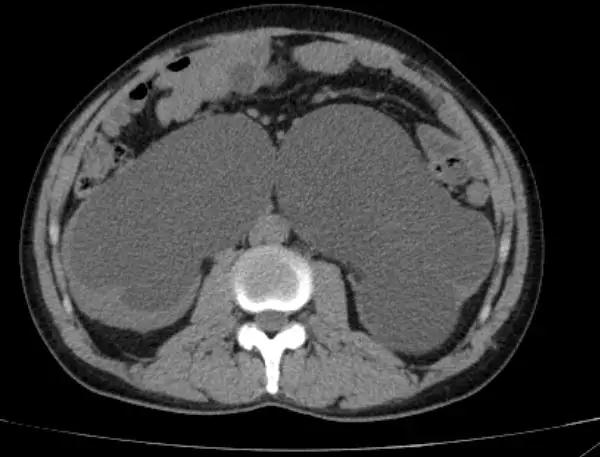

进一步完善泌尿系CT发现患者除了双肾重度积水,输尿管扩张之外盆腔有大量脂肪堆积

CT显示赵大哥双肾重度积水

盆腔脂肪明显增多,前列腺抬高,膀胱挤压变形